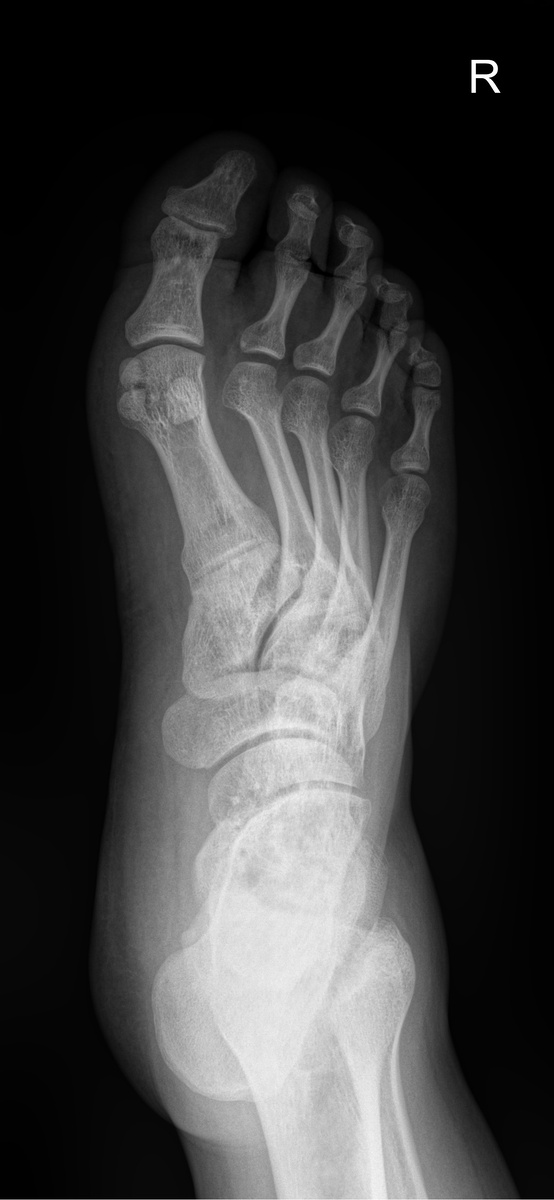

Рентгенограмма правой стопы в двух проектциях